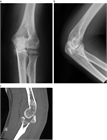

1. 橈骨頭骨折、橈骨頸部骨折の解剖学的特徴を把握する。

1. 橈骨頭骨折、橈骨頸部骨折は上腕骨小頭と橈骨頭が衝突して生じる。

1. 成人では橈骨頭に加え橈骨頚部も骨折しやすいが、小児では多くが橈骨頚部骨折である。